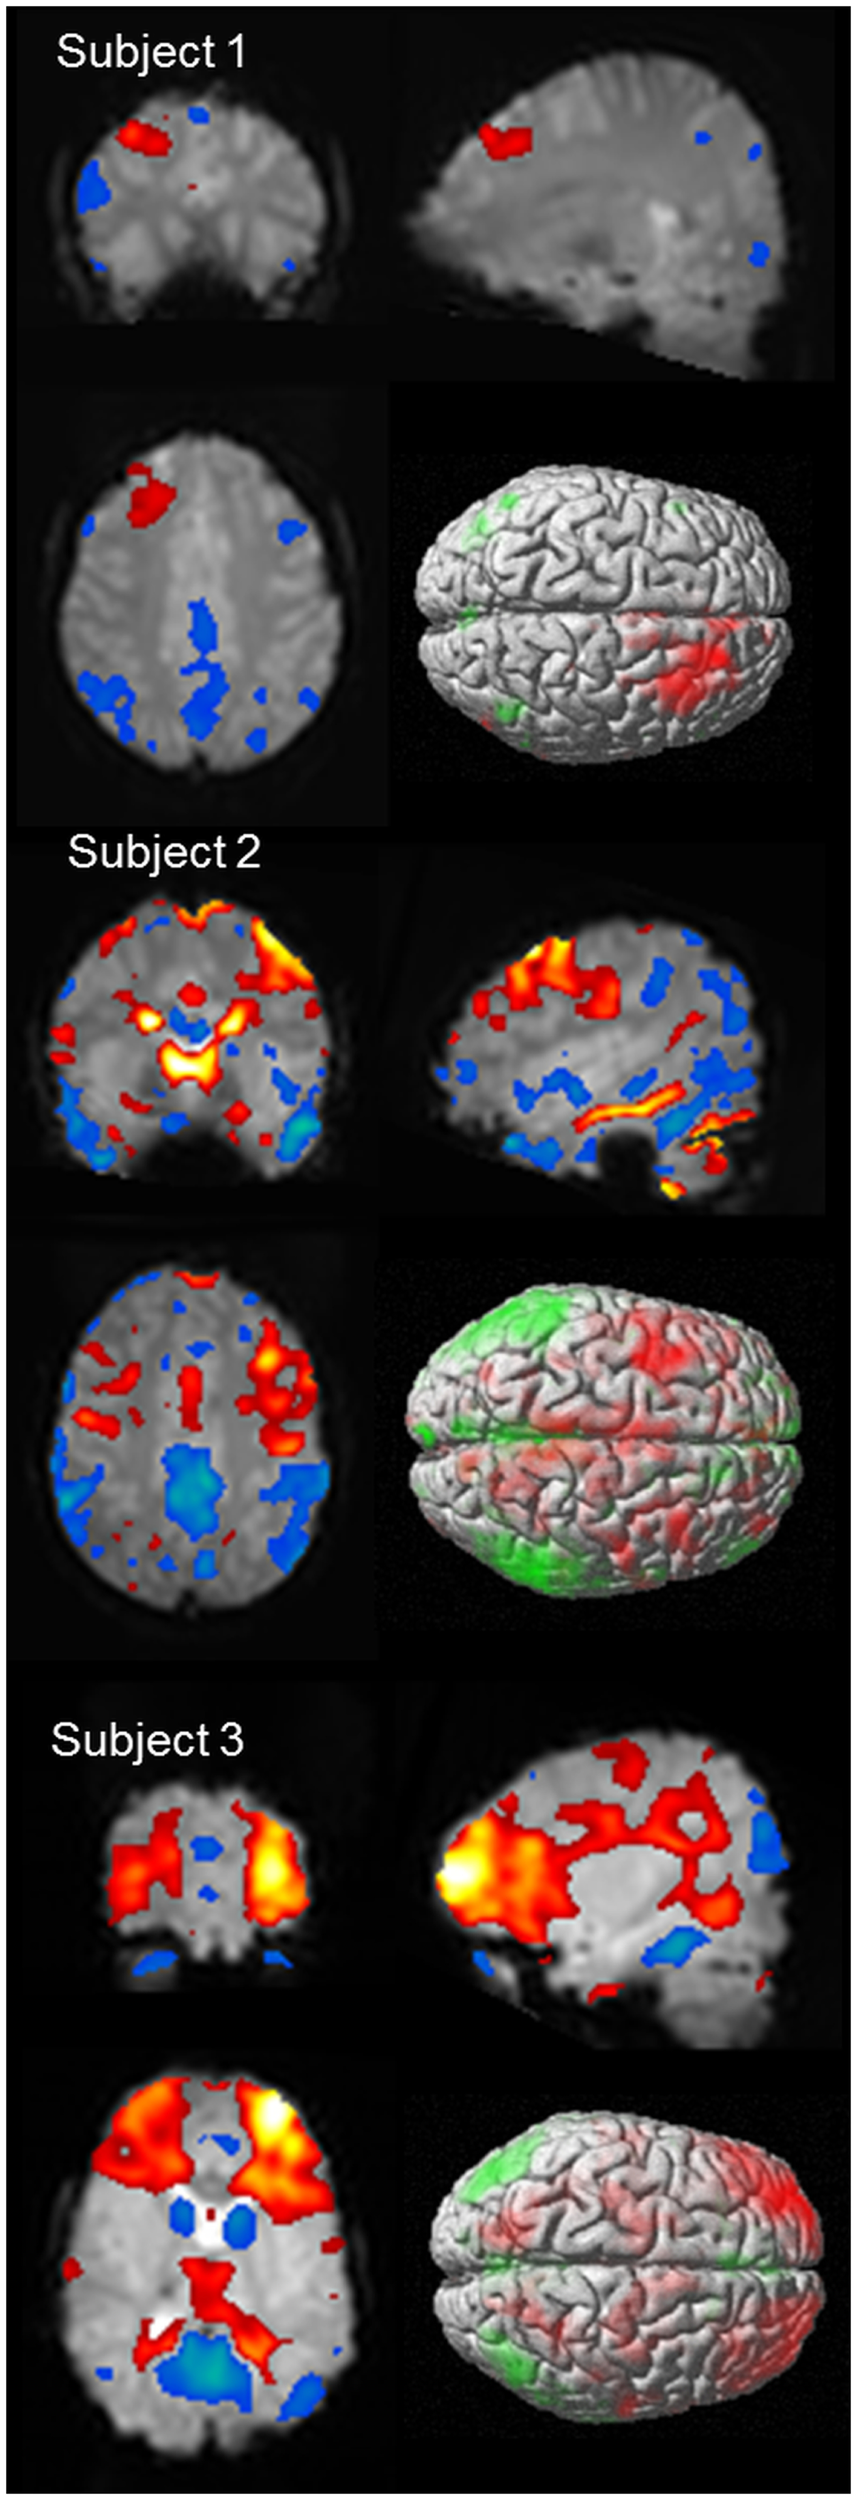

As discussed above, it would be expected that BOLD signal change would be seen in the frontal cortex as a consistent finding, given the observations made in animal models, as well as observations from electrophysiology. Negative BOLD change has been identified in the mesial frontal and anterior cingulate cortex in several studies (55, 56, 65, 66), which is not surprising given this region is a component of the DMN. Focal cortical BOLD change may be seen in individual cases (55, 65, 68), and it has been suggested that there may be subject specific changes in BOLD signal, which are consistent within individuals but vary from subject to subject (68). Another possibility is that frontal cortical BOLD change may reflect differences in sub-groups of patients with absence epilepsy (66). What is clear is that BOLD signal in the frontal lobe is influenced by AS (see Figure 4 for individual case results). When using a standardized event-related analysis of a group or individual, this may appear as increases, decreases, or no change. However, in group and individual analyses of BOLD time course, there are clear increases in BOLD signal in frontal cortical networks occurring prior to, co-incident with, or following the event onset. This is highlighted in our paper on sub-group differences in frontal cortical BOLD in which the division into frontal negative or frontal positive was dependent on the timing of the BOLD signal increase relative to the event onset, not whether BOLD signal increased or decreased (66). Given the wealth of clinical, electrophysiological, and functional data highlighting the importance of frontal lobe activity in seizure generation, it is important for fMRI techniques to better explore the contribution of frontal lobes to seizure generation.

Figure 4

BOLD signal change for three subjects showing variability of cortical BOLD change (figure previously unpublished). Color maps of positive BOLD (red to white: 0 to +10) and negative BOLD (blue to green: 0 to −10) change superimposed on subjects mean EPI image are displayed in three plains (p < 0.001). A single surface rendered image is also displayed demonstrating the cortical surface involved. Subject 1: 16 years female with onset of AS at age 5 who developed refractory AS and GTCS. EEG-fMRI of 6 (14 s) bursts of interictal activity. Subject 2: 13 years male with onset of AS at age 8 who achieved seizure control on mono-therapy. EEG-fMRI of 11 AS (105 s). Subject 3: 5 years female with AS since 4 who achieved seizure control on mono-therapy. EEG-fMRI of 6 AS (83 s).